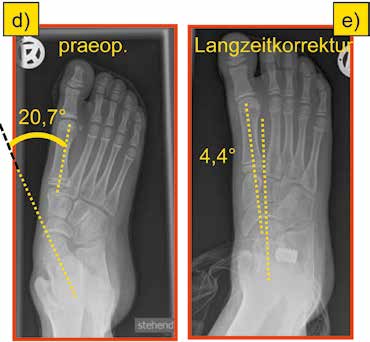

An einem plakativen Korrekturbeispiel (männlicher Patient, Operation im Alter von 10 Jahren) werden die Achsen- und Winkelverhältnisse in der Sagittal- und Horizontalebene vor und nach der Arthrorise gezeigt bzw. unter Anwendung gängiger Mess-Verfahren dokumentiert.

Der Talokalkanearwinkel nach Costa-Bartani zeigt eine sehr gute Korrektur des Fußes in der Sagittalebene mit einem Korrekturausmaß von 23° (präoperativ 32° – postoperativ 55°) (Abb. 1a u. c).

Der Tarsometatarsalwinkel I nach Hamel verdeutlicht die Aufrichtung des Talus und damit die funktionelle Ausrichtung auf das Metatarsale I. In dem gezeigten Beispiel kommt es zu einer Korrektur von annähernd 40° (präoperativ 39,6° – postoperativ 1,5°) (Abb. 1a u. c).

Der Talus-Neigungswinkel beschreibt die Korrektur des Talus obliquus und zeigt 24° Aufrichtung des Talus im Verhältnis zur Bodenfläche (präoperativ 47,8° – postoperativ 23,5°) (Abb. 1a u. c).

Im Unterschied dazu wird die Einstellung des Calcaneus in der Sagittalebene im gezeigten Fall nicht beeinflusst (präoperativ 18,9° – postoperativ 19,2°) (Abb. 1a u. c).

In der dorsoplantaren Betrachtung des Knicksenkfußes als „Pes abductus” zeigt der Winkel zwischen der Längsachse des Talus und des Metatarsale I den Korrektureffekt der Arthrorise mit annähernd 16° (präoperativ 20,7° – postoperativ 4,4°) (Abb. 1d u. e).

Die Betrachtung der Ergebnisse zeigt eine suffiziente Ausrichtung des Talus zum Metatarsale I in der Sagittalebene wie in der dorsoplantaren Darstellung. Diese Korrektur der knöchernen Strukturen bleibt nicht ohne Auswirkung auf die Längenverhältnisse der Sehnen mit dem beschriebenen konsekutiven Spitzfuß und der damit empfohlenen temporären Absatzerhöhung (Abb. 1b).